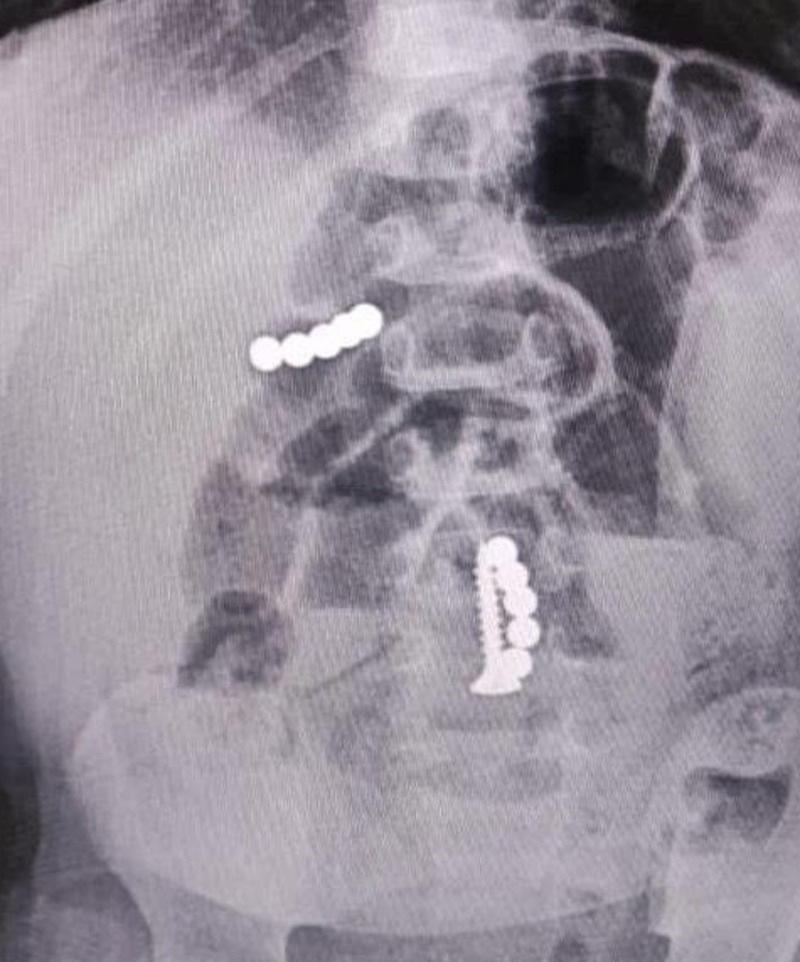

Ставропольские нейрохирурги провели две операции по установке биополимерных имплантатов вместо повреждённых межпозвоночных дисков. Такие конструкции называются кейджами. По своим характеристикам они максимально похожи на ткани человека.  Подобные операции стали возможны благодаря нацпроекту «Здравоохранение». Его реализацию курирует минздрав региона. Средства на оказание высокотехнологичной медпомощи выделяются из регионального бюджета.

В частности, врачи прооперировали 43-летнего местного жителя с избыточной подвижностью позвонков. Хирург Никита Чайкин выполнил процедуру с минимальным вмешательством и установил самофиксирующийся кейдж.

Ещё один 32-летний пациент оказался на операционном столе с межпозвонковой грыжей. Новообразование удалили. На её место поместили межтеловой биосовместимый имплант. Операцию провёл заведующий нейрохирургическим отделением №2 Виталий Косыгин.